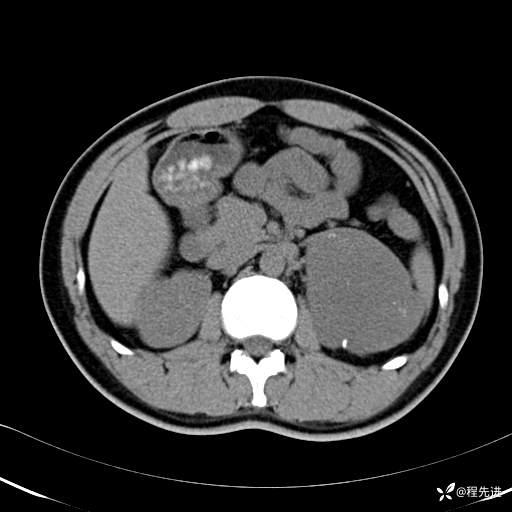

【腹盆】特别精彩病例|体检发现的左侧腹膜后占位期待您的精彩解读

患者年龄:25岁

简要病史:体检发现

CT平扫:(CT值:平扫,27HU,动脉期,27HU,门静脉期,31HU,平衡期,32HU)

门静脉期: